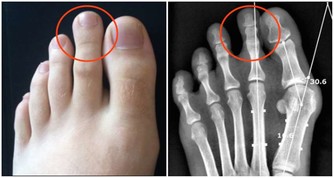

下面看一下這6種身體表現: 1、皮膚症狀:比如莫名的瘙癢、斑塊、疹子(不同於濕毒濕氣重等引起的瘙癢、濕疹)等,一些人還會出現指甲顏色、紋路的變異(要和灰指甲區分開來)。 2、乳房變異:這個主要和女性的乳腺癌有關,當腫瘤惡化時,就會侵犯乳房的正常腺體,導致出現乳房腫塊、乳頭溢液(特別是血性溢液)、橘皮樣皮膚等。